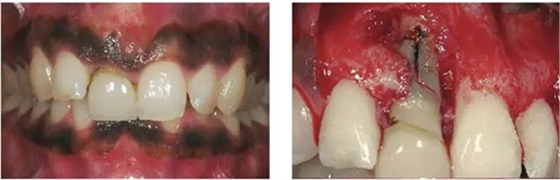

圖1、該病例顯示了厚齦生物型和中弧線形齦乳頭形態(tài)。右上中切牙由于牙根縱裂而需要拔除。由于該患牙伸長,使得軟組織量垂直向增加。牙齦色素沉著是個美學(xué)挑戰(zhàn)。

圖2、翻開全厚瓣可見明顯的牙根縱裂,唇側(cè)骨板2/3受到累及而缺損。